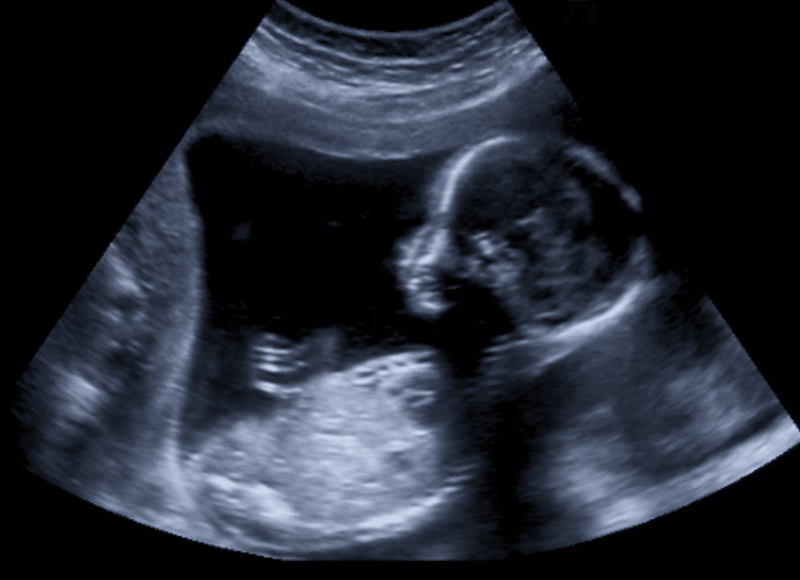

Two doctors of a private hospital in Noida have been charged with negligence that resulted in the death of a fetus in March, according to a report of the Uttar Pradesh Medical Council.

A Greater Noida-based couple, both software engineers, had approached the Sector 49 police station in March after the death of their yet-to-be-born at the Cloudnine Hospital in Sector 51. An FIR was registered under Indian Penal Code Section 304 (causing death by negligence) and the doctors named as accused. Ankit Garg had alleged in his complaint to police that doctors Pratibha Singhal and Ritika Dinanath had "delayed" in attending to his wife Shweta Kashyap when she was in labor and their "child died due to negligence".